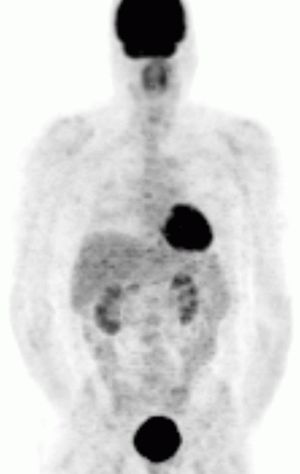

영상 검사로는 CT, MRI, 131I-MIBG 신티그래피, PET 등이 있다.[82] CT와 MRI는 종양의 위치, 크기, 주변 구조와의 관계를 파악하는 데 유용하다.[82] 131I-MIBG 신티그래피는 부신 외 원발 병변이나 전이 병변의 위치를 확인하는 데 사용된다.[88] MIBG는 노르에피네프린과 유사한 구조를 가져 종양 세포에 섭취되는 원리를 이용한다. PET 검사는 MIBG 섭취가 없는 경우에도 양성으로 나타날 수 있으며, 전이 병변 검색에 유용하다.[90] 특히, 68Ga-DOTA 유사체를 이용한 PET 검사는 소마토스타틴 수용체 영상 기법으로, 다른 기능적 영상 검사보다 우수한 성능을 보인다.[94][95][97]

전이성 크롬친화세포종은 종양 세포(크롬 친화 조직)가 정상적으로 발견되지 않는 곳에 존재하는 것으로 정의된다.[133] 가장 흔한 부신 외 전이 부위는 림프절, 폐, 간, 그리고 뼈이다.[135]

아래의 모든 잠재적 치료 옵션에도 불구하고, 최근 문헌에서는 (대부분의 환자에게) 전이성 크롬친화세포종이 천천히 진행된다는 점을 강조한다. 질병 부담이 최소인 환자의 경우, 질병 진행의 증거가 시각화될 때까지 치료를 보류하고, 질병을 모니터링하기 위해 빈번한 영상 검사를 시행하는 "관찰 대기" 접근 방식이 선호된다.[138]